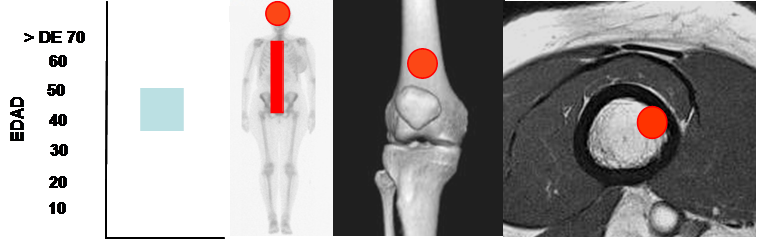

Fig 149 A. Hemangioma óseo.

Mayor frecuencia entre la 4º y 5º década. Predominio en el cráneo y columna.

Lesión metafisiaria, de ubicación excéntrica.